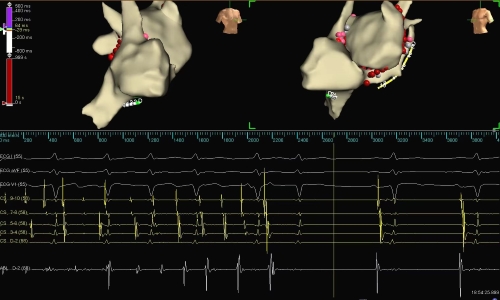

图2:在先进的标测系统和技术指导下成功消融房颤、患者恢复正常心律

此次手术采用雅培Ensite三维标测系统和国际上最新的LiveView标测技术,使用HD-GRID高密度标测导管进行心腔内基质标测,在湘雅三医院独创术式HOT-AF指导下进行高功率消融(50W/43℃)。双侧肺静脉电隔离成功后,行心房顶部及冠状窦内膜面、二尖瓣峡部线性消融,紧接着采用LiveView技术找到了左心耳和右心耳等多个驱动灶并对其进行消融,患者最终恢复窦律。再次行电生理检查和LiveView实时动态标测,证实消融线双向阻滞,手术成功。据悉,本例是湖南省首台采用Ensite LiveView标测技术的持续性房颤射频消融术,这也开创了湖南省新型动态标测系统的新纪元,进一步提高了复杂的持续性房颤手术成功率。